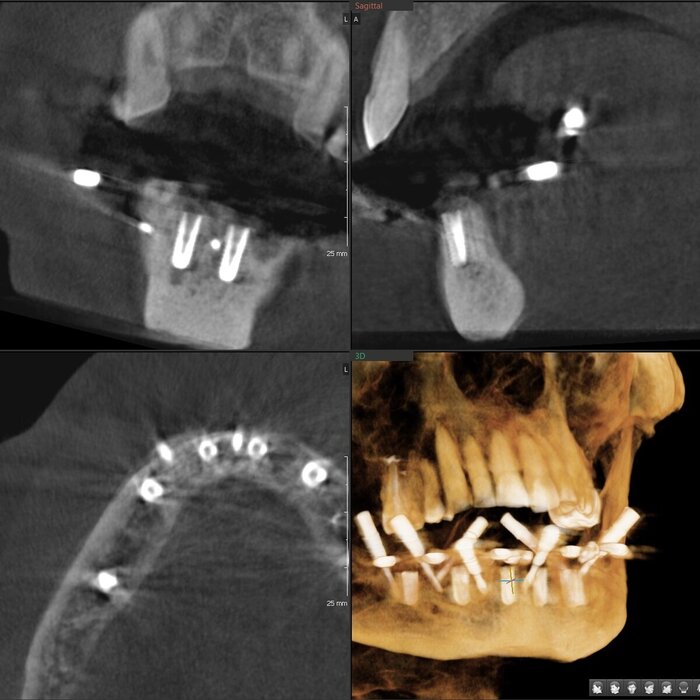

Пока верх не закончен, можно переходить к низу. Тут всё проще (как это часто и бывает). Выбор сделан в пользу тотальной работы на 6 имплантатах (сверху, по итогу, будет то же самое).

Для операции нам требовался снимок КЛКТ и цифровой слепок челюстей. Всё это пациент сделал в своём городе.

Мы распечатали шаблоны, которые помогал проектировать зубной техник Михаил:

Напомню, что шаблон не один, их много - базис, для сверления и досверливания (2 штуки), постановка и ложка. К базису крепятся составные части магнитами. Хотя, когда случаются особые случаи, всё крепится по-старинке, острыми и длинными "копьями" - пинами.

Часа через 2.5-3 имплантаты были установлены.

Результат такой - торки получены эталонные везде, кроме двух крайних имплантатов слева (3.4 и 3.6). Но не страшно, сверху зубов-антогонистов нет, нагрузки на протез не будет серьёзной. Да и "всё на 6" прощает подобное.

Протез будет с розовой десной и-за дефицита тканей (FP3).